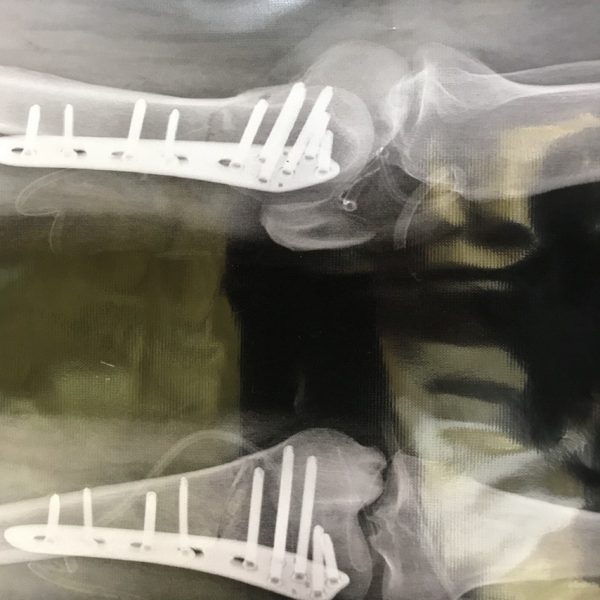

Correcting the deviation of the knee brace from above the knee.

which is done in certain cases, and in these patients, contrary to common cases, it is the cause of the deviation of the knee from the femur.

diagnosisBracket knee deviation

treatmentSurgery and care